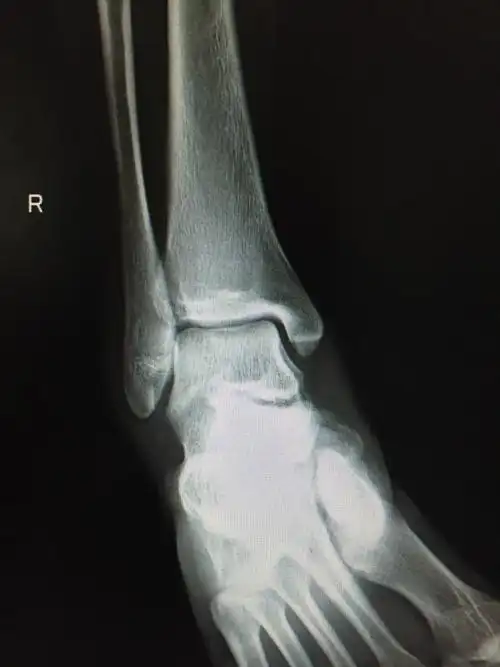

踝关节外侧副韧带损伤合并撕脱骨折的治疗

陈旧外踝韧带撕脱骨折的碎片?